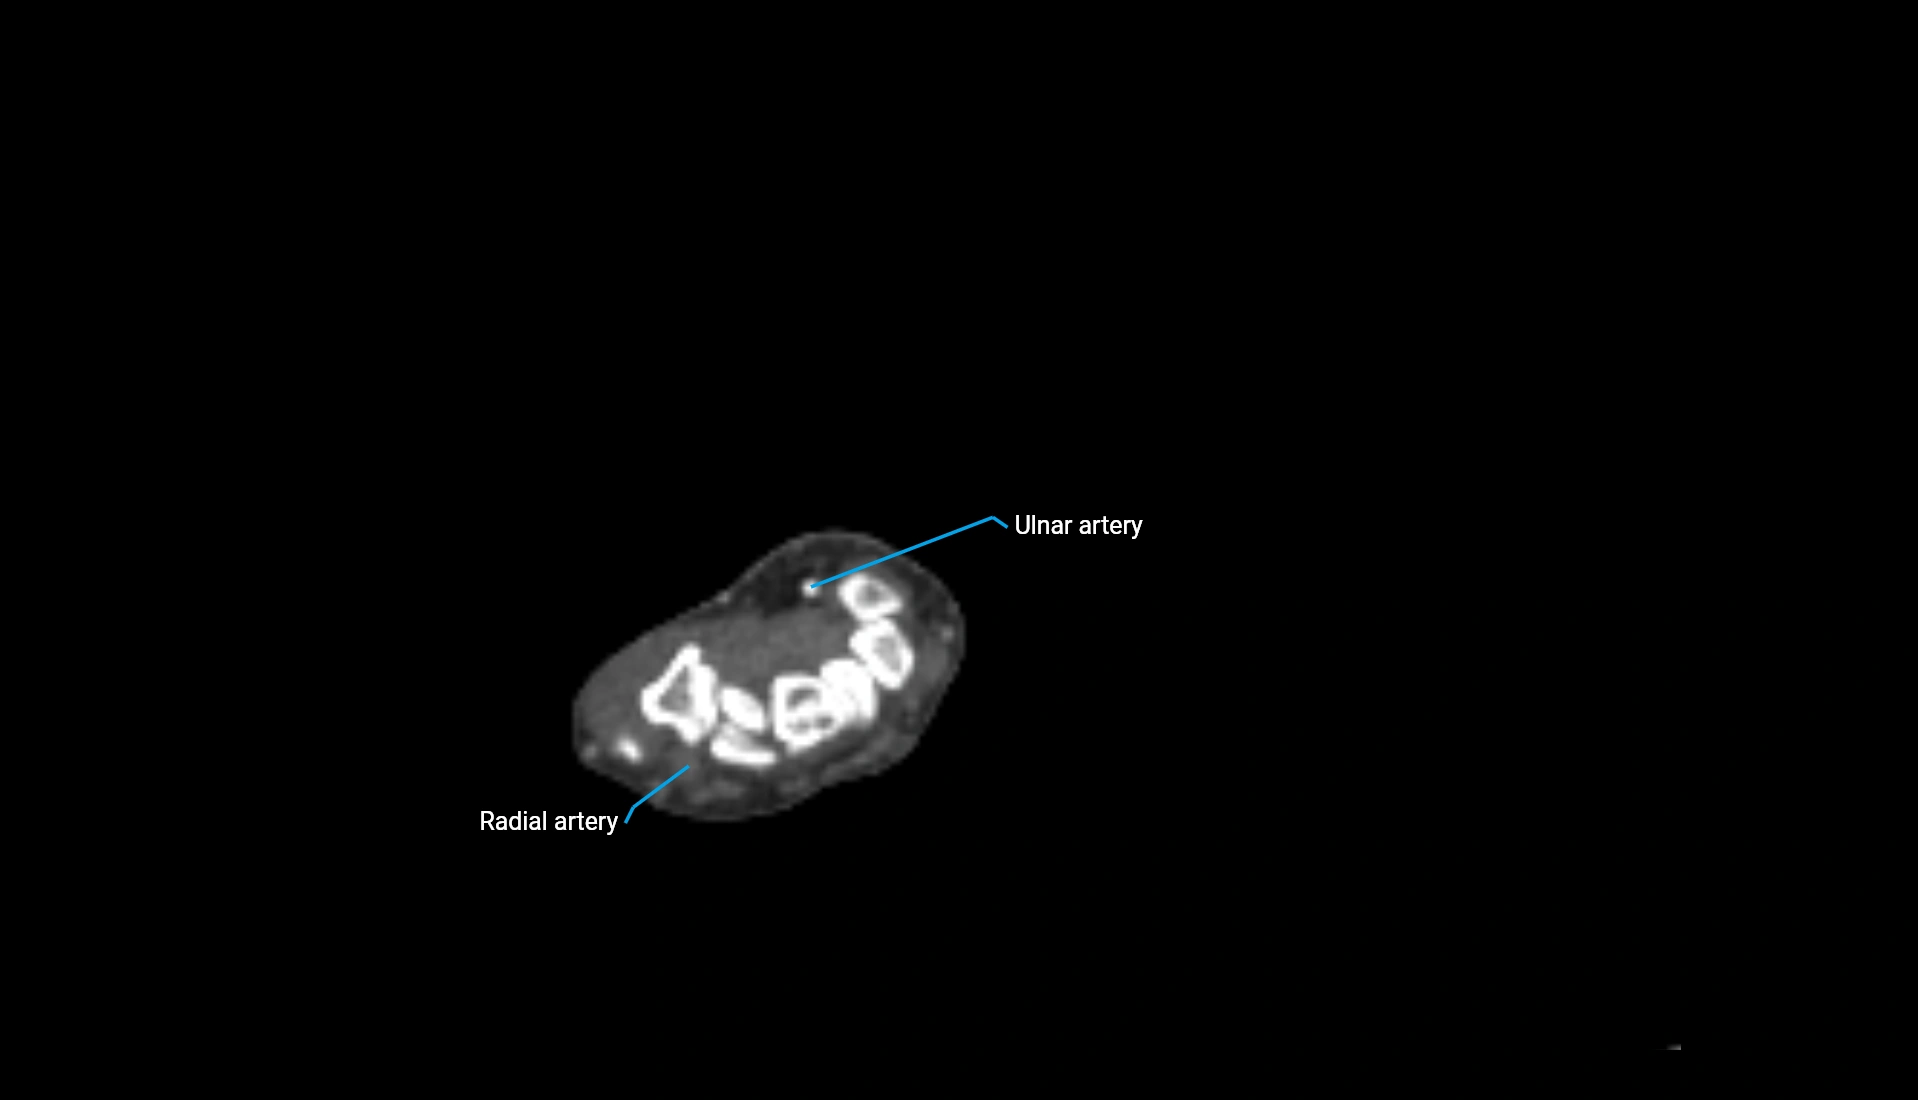

MRI image

image